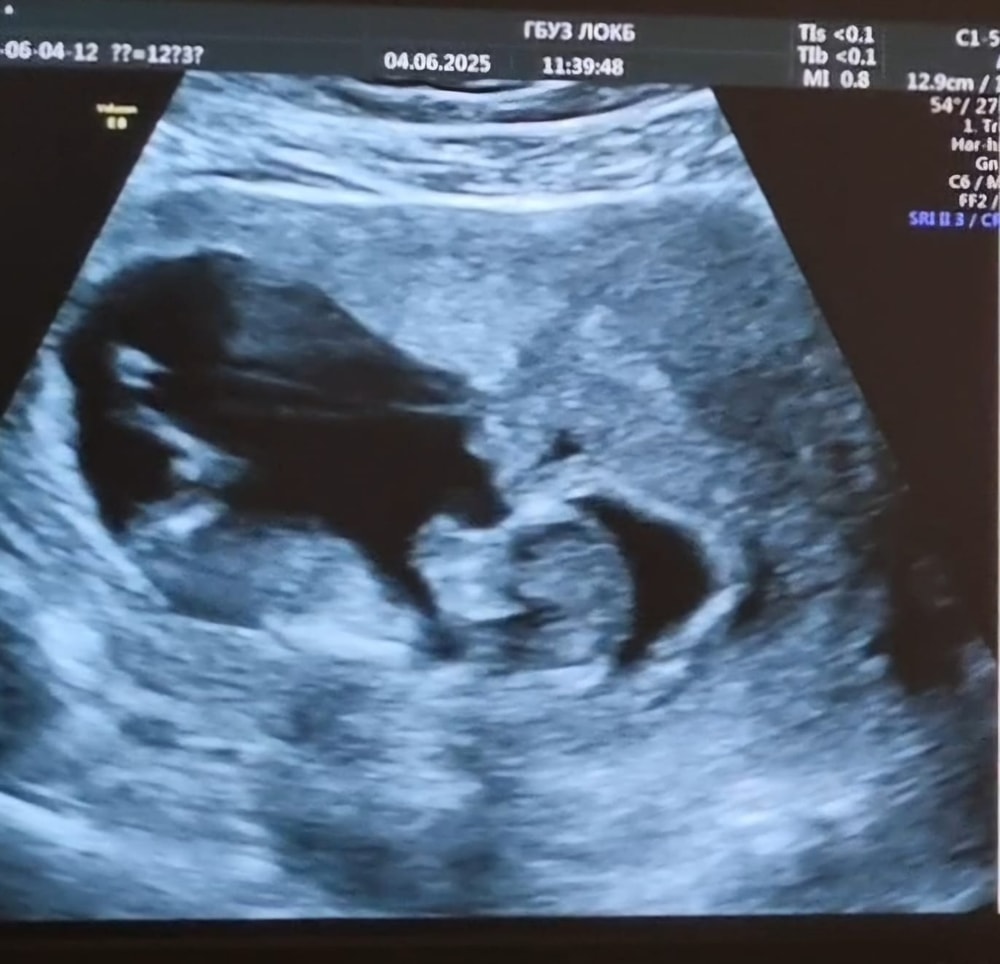

- 2 скрининг